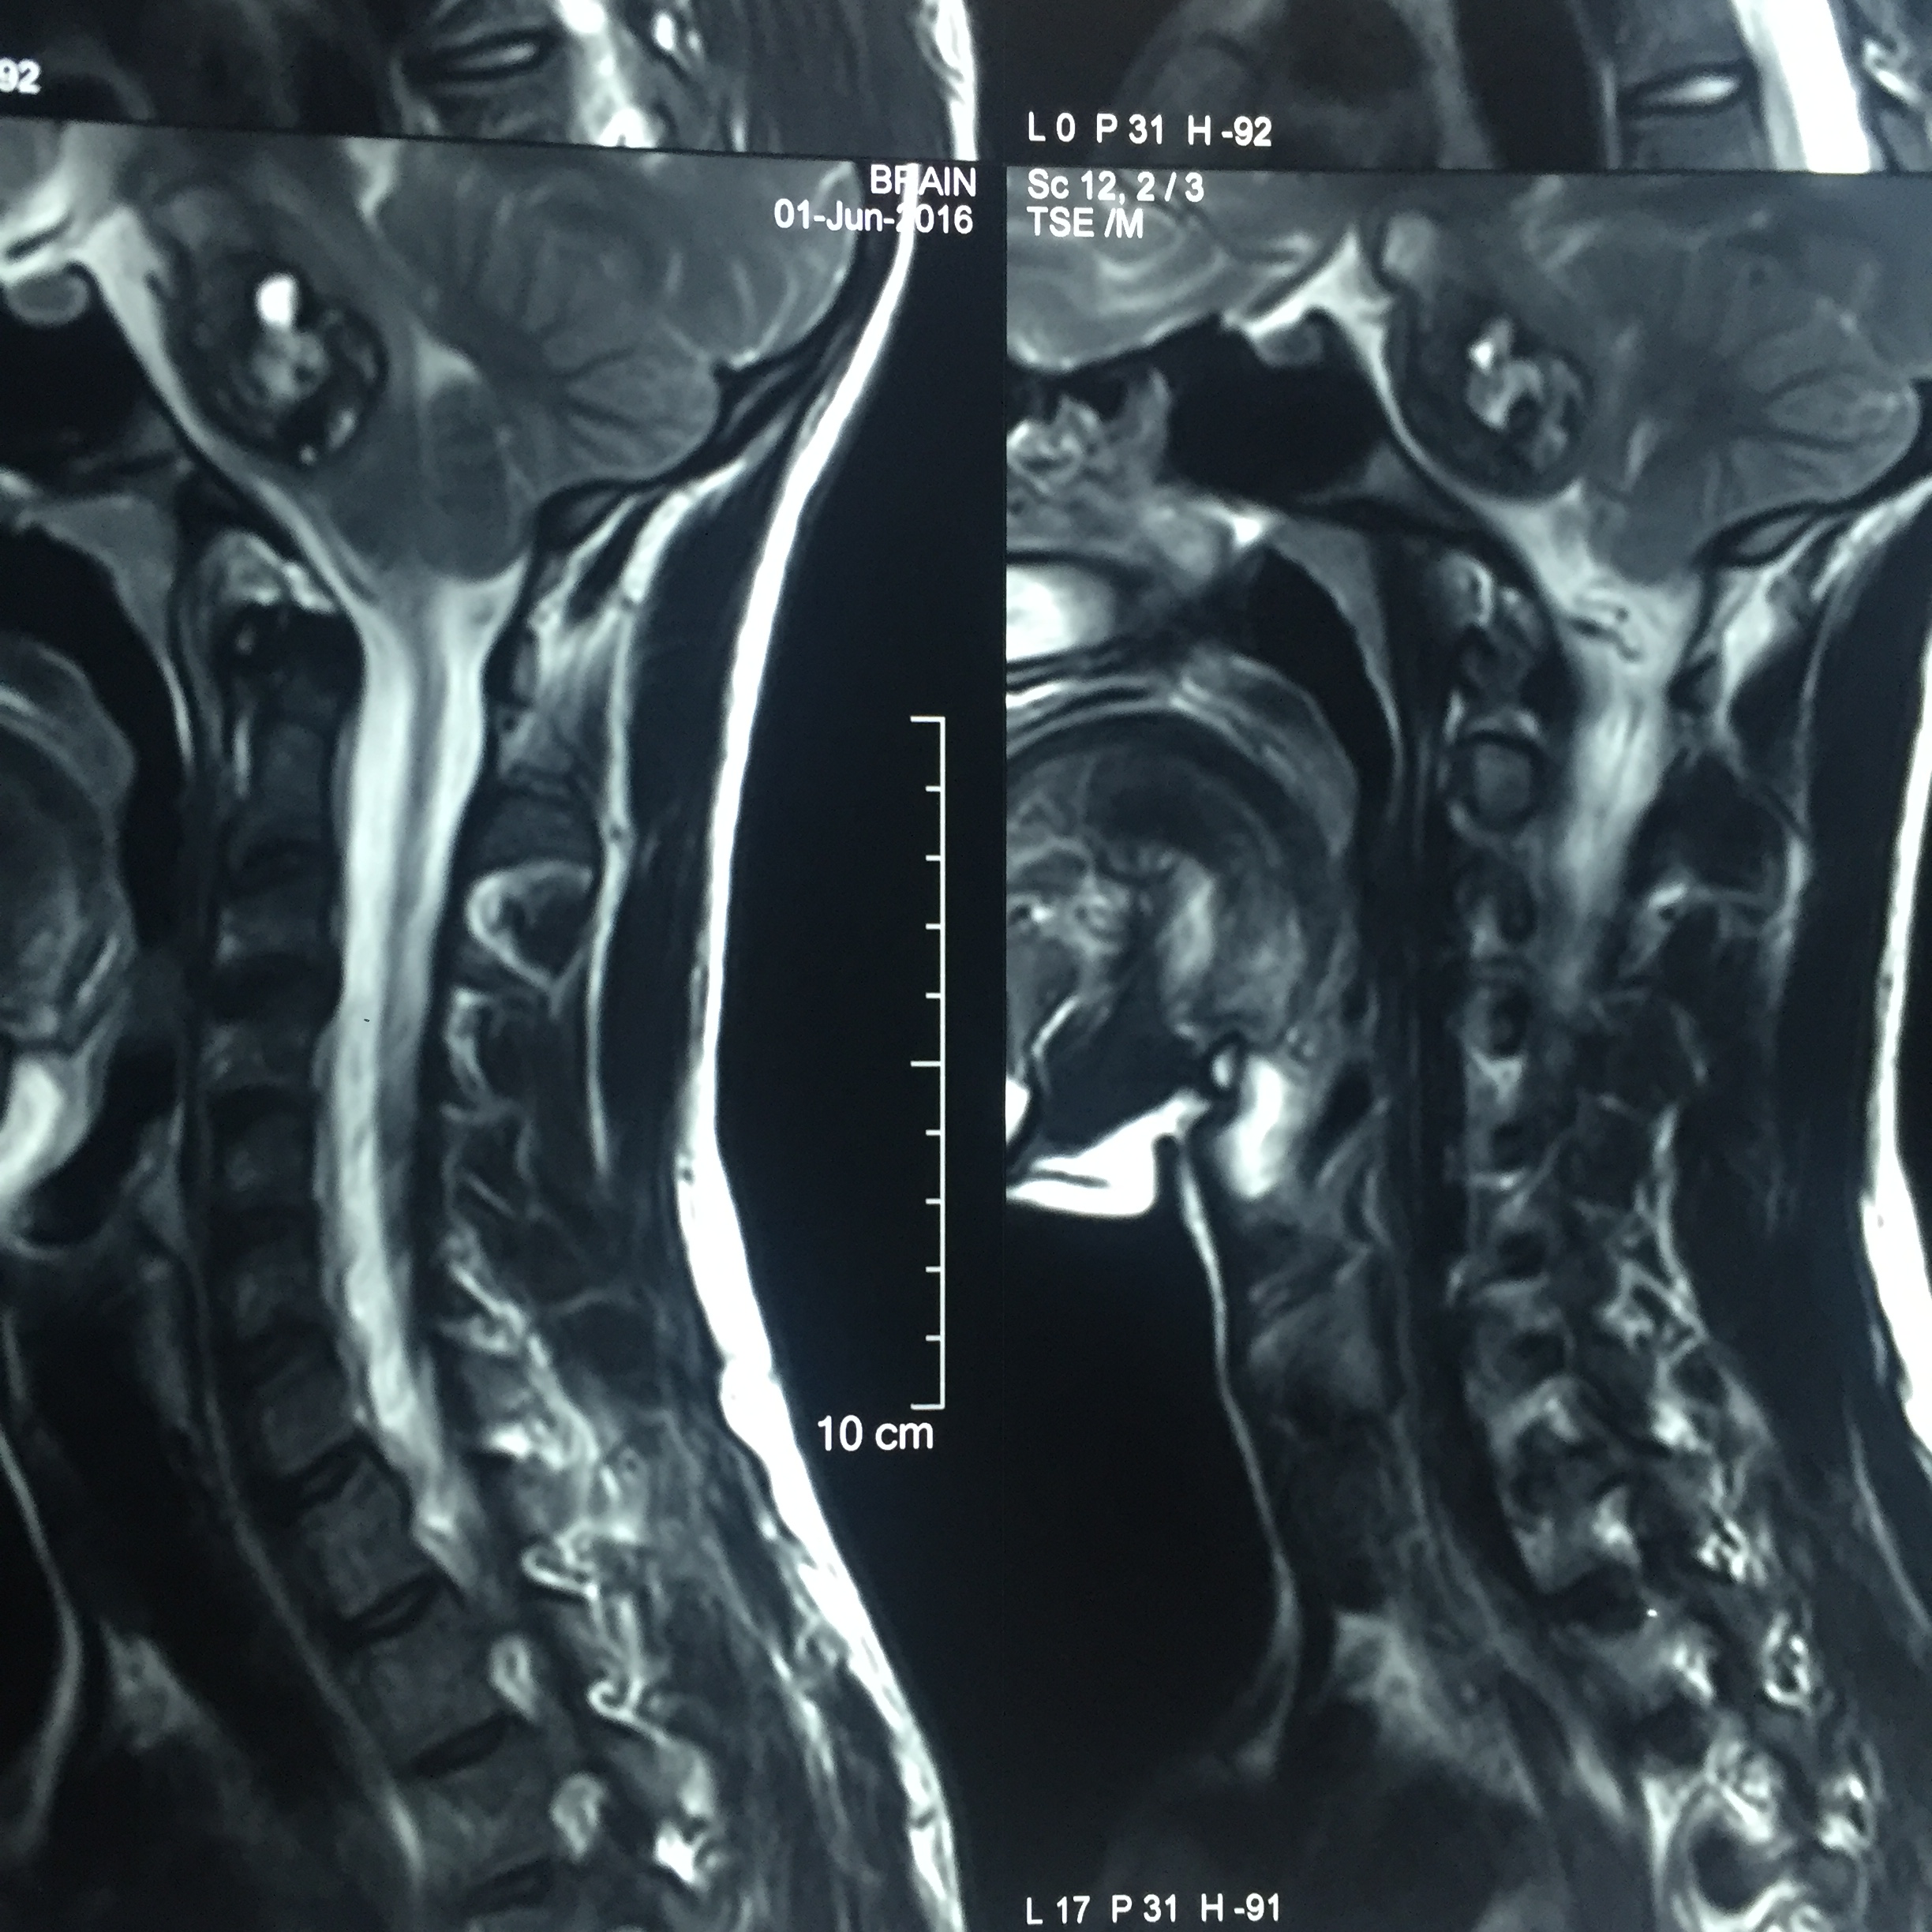

Intramedullary Spinal Tumour : Surgery- Microsurgical excision of spinal tumor